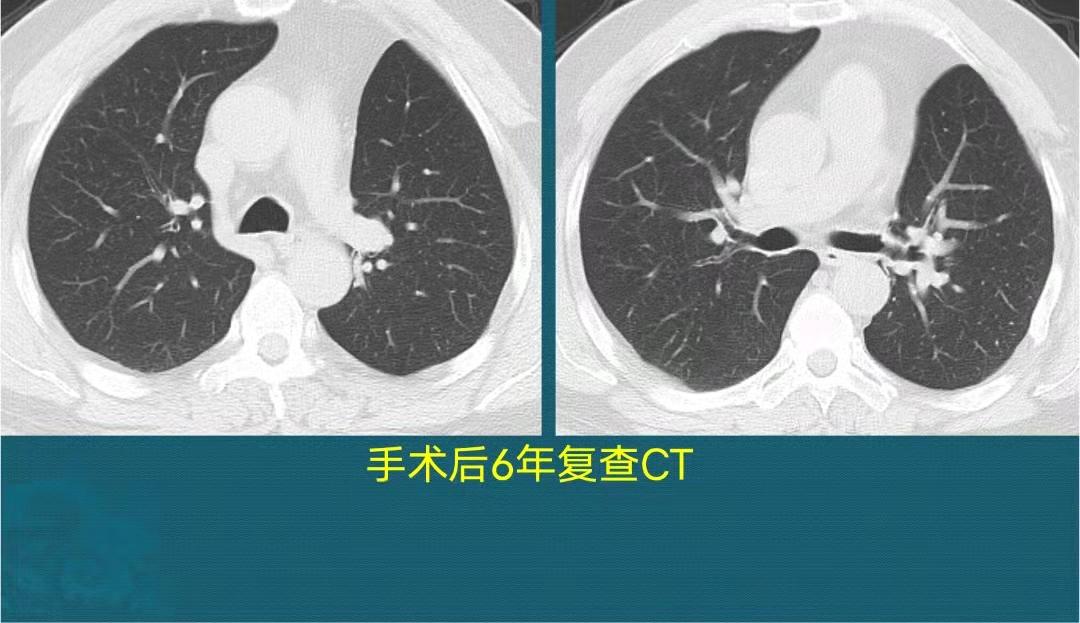

手术后6年复查,恢复很好:

人类一共有5叶肺,左边两叶右边3叶,他失去了左边一个肺叶,但成功推掉了地府归队通知,延长了几十年的地球寿命,很幸运!